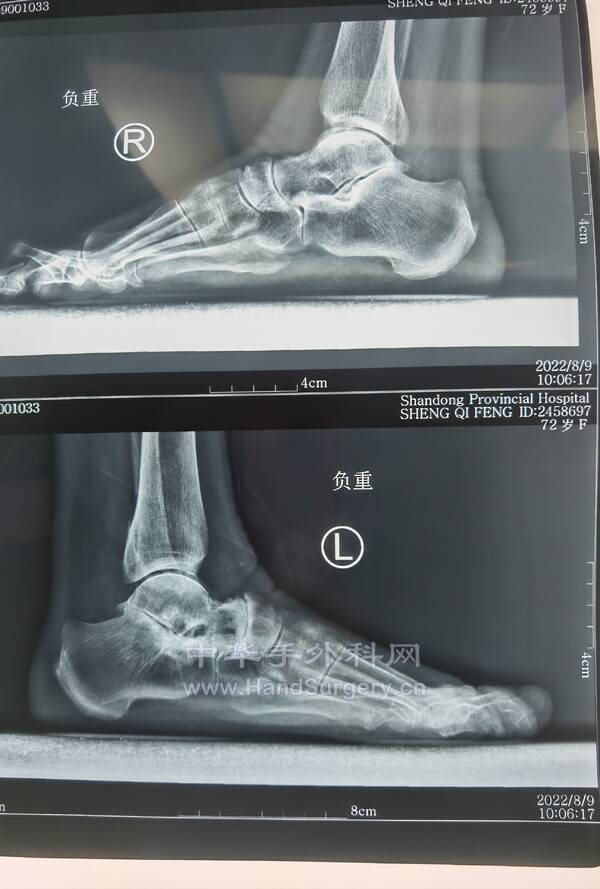

今日得偿所愿,上午跟着老师参观双侧青少年柔韧性扁平足微创扁平足制动器矫正术,双侧副舟骨切除胫后肌腱止点重建术的

13岁男性患者,用的威高扁平足制动器(但大博2代扁平足制动器相对较好)。

副舟骨切除,用直径3.0mm可吸收螺钉固定,与胫后肌腱加固缝合,腱骨缝合,用2.5mm克氏针在舟骨上打孔,放入强生直径3.0mm可吸收铆钉(丝线亦为50%可吸收线),远端与胫后肌腱编织缝合加固!术后6周不能行走。